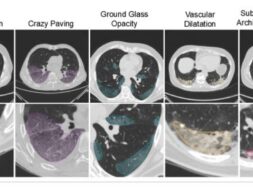

Η εφαρμογή της τεχνητής νοημοσύνης στη διαδικασία του triage (της διαλογής των ασθενών) μπορεί να συνδράμει στη βελτιστοποίηση των εσωτερικών νοσοκομειακών πόρων και της θεραπευτικής διαδικασίας του ασθενούς, η οποία θα λαμβάνει χώρα με την αναγκαία απομόνωση, ανάλογη του επιπέδου σοβαρότητας της λοίμωξης. Ο αλγόριθμος, θα μπορούσε να αναλύσει γρήγορα εικόνες υπολογιστικής τομογραφίας και έτσι να κατηγοριοποιήσει τους ασθενείς με COVID-19 σε τρεις ομάδες με κριτήριο την σοβαρότητα της νόσου: η πρώτη ομάδα περιλαμβάνει άτομα που μπορούν να συνεχίσουν την απομόνωση στο σπίτι, η δεύτερη ομάδα τους ασθενείς που χρήζουν νοσηλείας και η τρίτη ομάδα περιλαμβάνει τους πιο σοβαρά προσβεβλημένους ασθενείς. Οι τελευταίοι όντας εκείνοι που πρέπει να νοσηλευτούν έγκαιρα στην μονάδα εντατικής θεραπείας. Η μέθοδος θα μπορούσε να βελτιστοποιήσει τη διαχείριση του τεράστιου όγκου δεδομένων που παράγεται διαρκώς από τις νοσοκομειακές εγκαταστάσεις.

Η χρήση της τεχνητής νοημοσύνης στην διαγνωστική ανάλυση

Την μελέτη που δημοσιεύθηκε στο International Journal of Environmental Research and Public Health θα ακολουθήσει μια δεύτερη φάση δοκιμών και επικύρωσης του αλγορίθμου στην κλινική πρακτική. Η χρήση της τεχνητής νοημοσύνης, σε μια εποχή έκτακτης υγειονομικής κατάστασης όπως η τρέχουσα, θα μπορούσε να επιτρέψει μια ταχύτερη ανάλυση των διαγνωστικών εικόνων αποτελεσματικότερη από εκείνη ενός ειδικού. Επιπλέον, η έγκαιρη ταυτοποίηση του υψηλού ή χαμηλού κινδύνου του μεμονωμένου ασθενούς μπορεί να βοηθήσει στον εξορθολογισμό του τρόπου της διαχείρισης των θαλάμων και της φροντίδας των ασθενών νωρίτερα από τα αποτελέσματα των κλινικών ή εργαστηριακών εξετάσεων, για τα οποία ο χρόνος αναμονής είναι μεγαλύτερος.